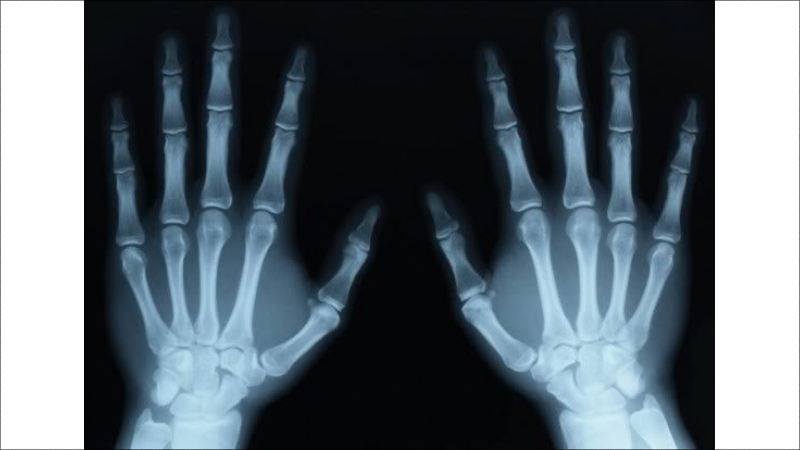

Để chẩn đoán viêm khớp ngón tay, các bác sĩ cần quan sát triệu chứng trực tiếp trên ngón tay của bạn, kết hợp với các hình ảnh cận lâm sàng như chụp X-Quang.